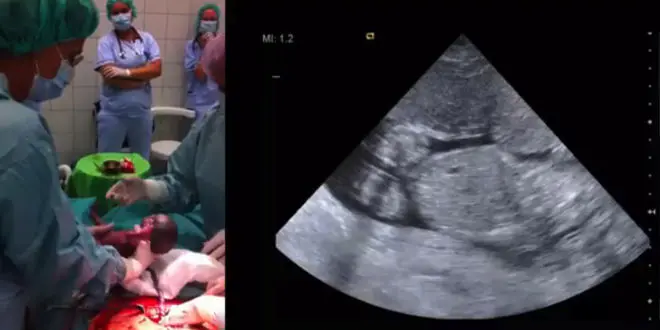

Selon les échographies, le fœtus porté par la jeune femme était toujours en mouvement. Une telle situation n'étant pas sans précédent, les médecins savaient qu'il était possible - bien que risqué - de maintenir ce fœtus en vie in utero dix à vingt semaines supplémentaires pour permettre son développement, puis de le placer en couveuse.

Quatre-vingt dix jours après l'entrée de la mère en soin intensif, soit à la vingt-septième semaine de grossesse, une césarienne a été pratiquée pour mettre au monde l'enfant. Pesant 1420 grammes, celui-ci a été placé en couveuse. Plusieurs mois plus tard, il a rejoint sa famille et serait aujourd'hui en parfaite santé.